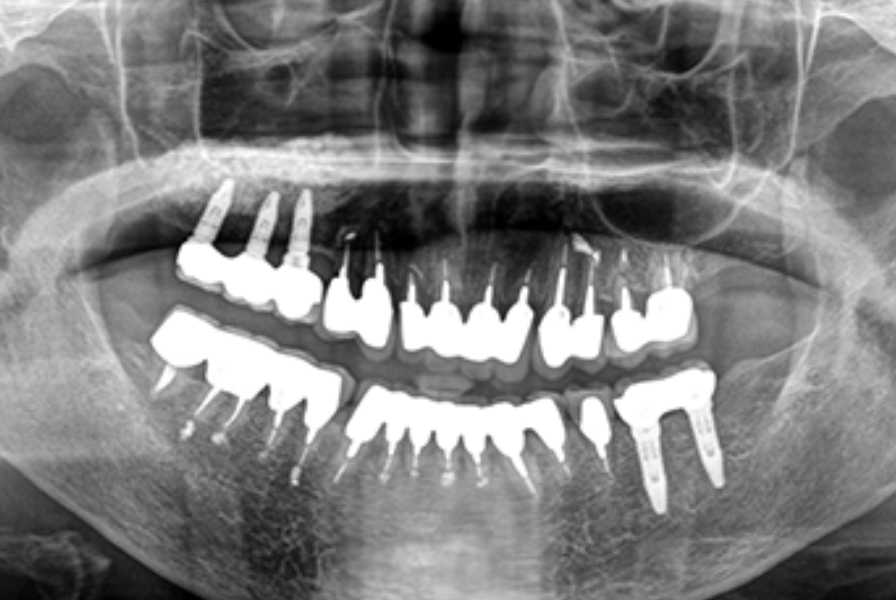

林歯科医院では、インプラント治療において高い専門性と豊富な経験を持っています。天然歯以上の咬合力を持ち、長期間使用できるインプラントは、残存歯に負担をかけることなく、自然な噛み心地を実現する優れた補綴治療法です。

林歯科医院のインプラント治療の特徴は、永久固定方式を採用している点にあります。他院でよく見られる定期的なネジ締めが必要なスクリュー固定方式ではなく、メンテナンスフリーの方式を取り入れることで、患者様の負担を軽減しています。また、京セラ製インプラントを使用し、地域でも多数の症例実績を誇っているのです。

インプラント治療では骨量が少ない場合に施術が難しくなることがありますが、林歯科医院では骨造成技術を駆使することにより、通常では対応が困難な症例にも対応することが可能となっています。インプラント治療用の専用機器を用いて周辺組織へのダメージを最小限に抑え、安全かつ予知性の高い治療を提供しています。これらの総合的なアプローチにより、患者様の生活の質を向上させる確かな治療が実現できるのです。